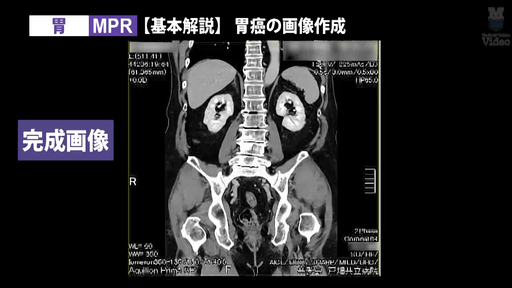

3D画像作成の人気シリーズに、「胸郭出口症候群(TOS)」と「胃」の新作を追加。CT撮影から3D画像作成までの流れを、実際の画面キャプチャを交えて徹底解説します。

● 3D画像製作 胃 MPR・VR